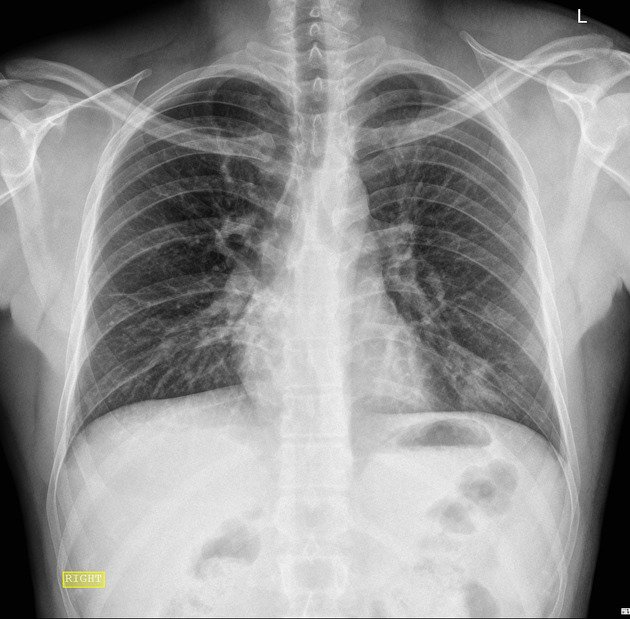

Cough, fever, cold, and body pain since yesterday

Diagnosis: Pneumonia

Certainty: Almost Certain

Author: Sadia Noreen

Date Published: Jan 23, 2025

Disease Specialty: Pulmonology

Image Type:

X Ray